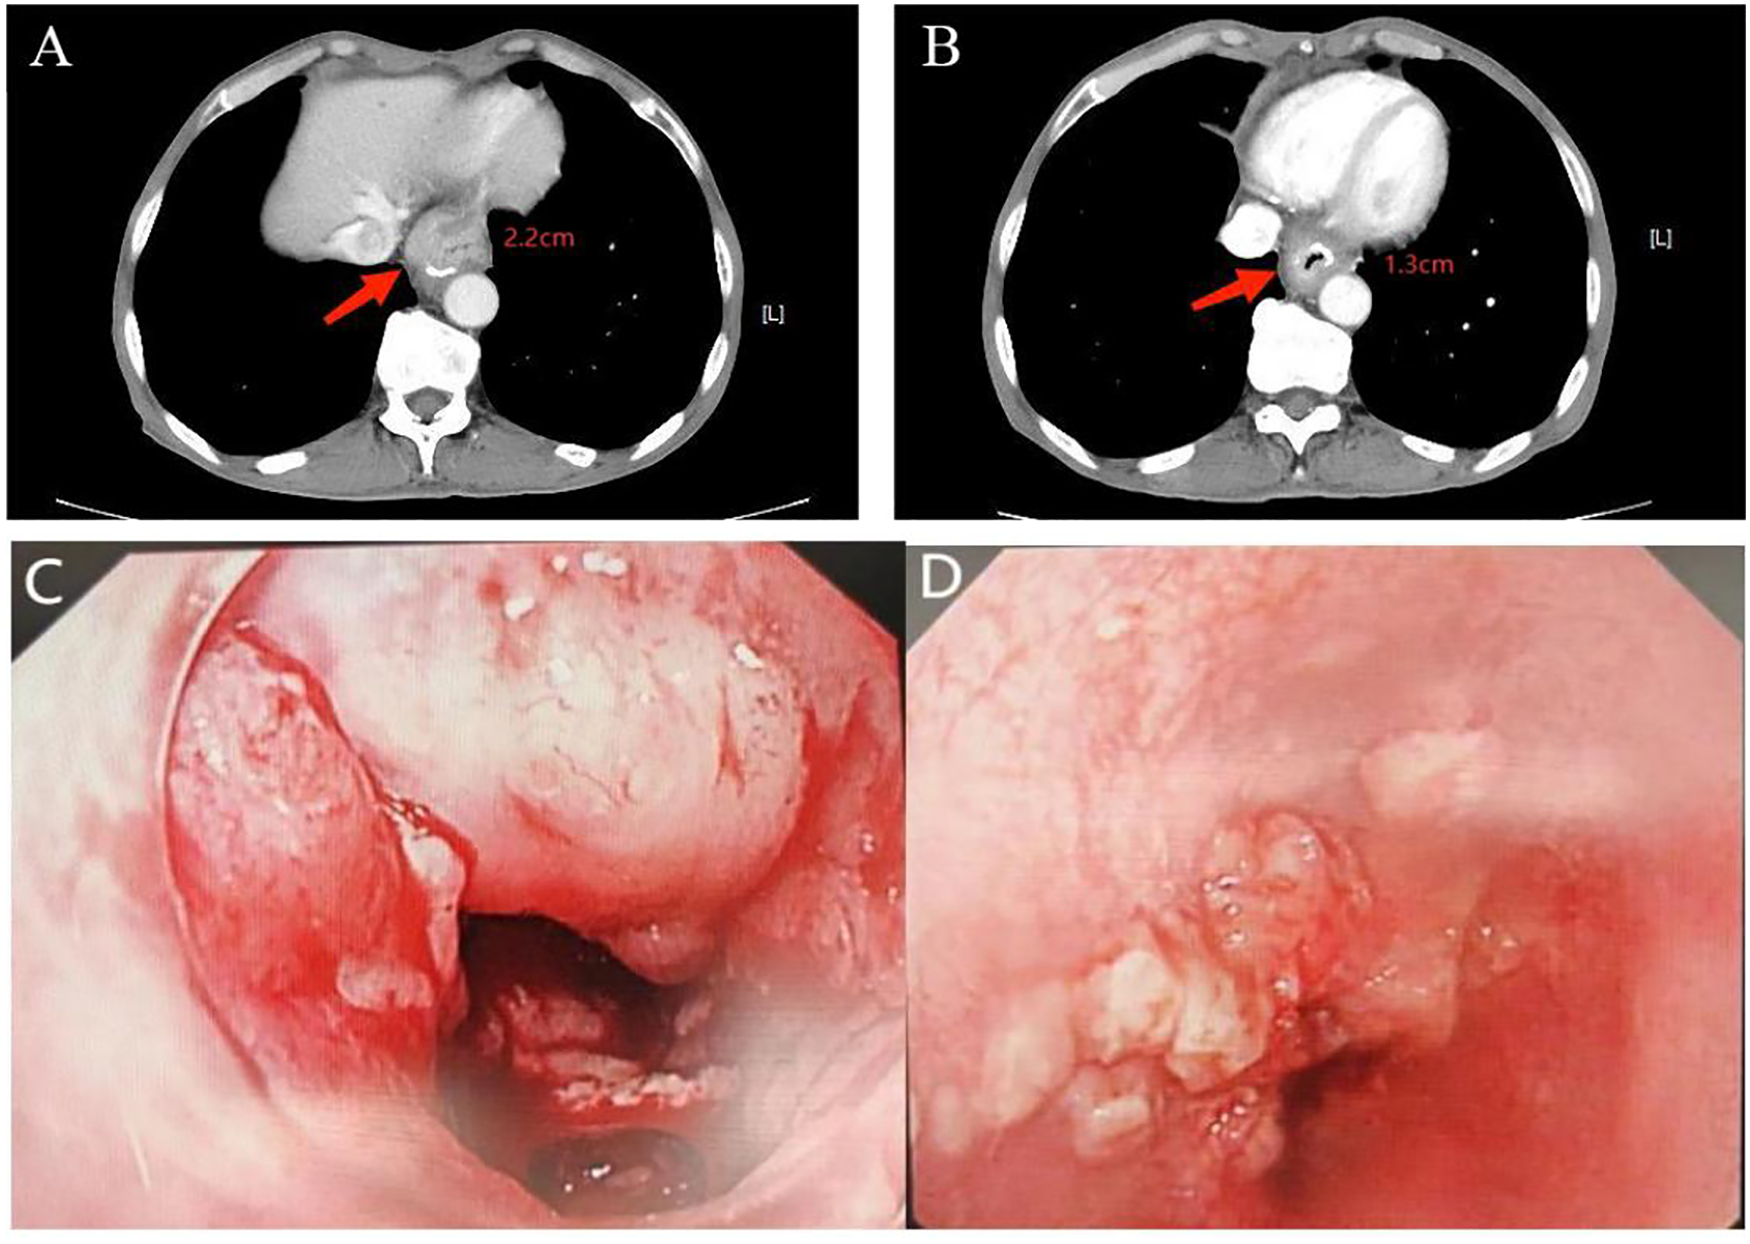

In February 2023, he was admitted to our department with an worsen eating obstruction. Chest and abdominal computed tomography (CT) scan showed cardia recurrence and multiple metastases in liver, peritoneum, abdominal cavity and retroperitoneal lymph nodes. Sintilimab (200mg, intravenously every three weeks) combined with nanoparticle albumin-bound paclitaxel(300mg, intravenously every three weeks) was admitted as first-line treatment after recurrence. After 4 cycles of chemotherapy plus ICI therapy, the patient´s metastases were significant shrink (Figure 1), but the cardia lesions were almost unchanged. As the patient strongly requested further relief of eating obstruction, we implemented exploratory local injection of H101 into recurrent cardia lesion by painless gastroscopy with the patient’s full knowledge and consent. Since June 9, 2023, H101 (5.0×1011 virus particles/0.5ml every time) was multipoint injected by painless gastroscopy every six weeks (8), 1 day before Sintilimab in each cycle. We observed on CT and gastroscopy images that the cardiac lesion were significantly reduced after two H101 treatment (Figure 2). Meanwhile, the patient´s eating obstruction symptom was subsequently relieved. Before and after two H101 treatment, we biopsied the cardia lesions and performed immunohistochemical staining of CD4+T cells and CD8+T cells respectively, results revealed a significant promotion of CD4+ T cell infiltration after H101 treatment (Figure 3). Unfortunately, no significant infiltration of CD8+T cells was found after H101 treatment (Figure 4). Then Sintilimab combined with S-1(60mg orally twice daily for 14 days) was admitted as maintenance antitumor therapy to date. (The timeline of treatments is shown in Table 1).

Figure 2

www.frontiersin.org

Figure 2. Comparison of cardia lesion thickness on CT and gastroscopy images before and after H101 treatment. (A) Before H101 treatment, the thickest part of the cardia lesion was about 2.2cm; (B) After H101 treatment, the thickest part was significantly reduced to 1.3cm; (C) Before H101 treatment, gastroscopy showed that the cardia lesions were large and protruding into the cavity; (D) After H101 treatment, gastroscopy showed that the cardia lesions were significantly reduced and the local stenosis was significantly improved.